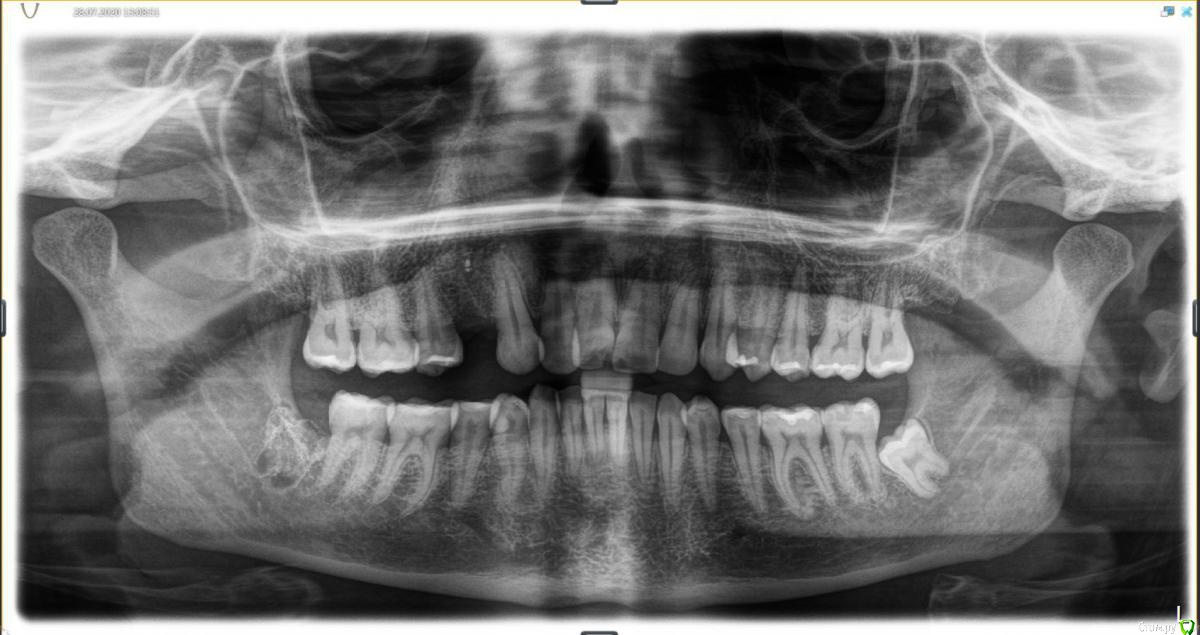

1. Московская клиника, врач работала с ассистентом, оборудование в клинике есть. Сделали контрольный снимок после – прилагаю к теме.

Фото ОПТГ до и после удаления прилагаю.

(Есть также файл КТ до удаления, но я хз, что из него надо брать, так что заскринила, что смогла).

post-60858-0-92958200-1596146772_thumb.jpg

post-60858-0-24490800-1596146821_thumb.jpg

post-60858-0-95972000-1596146826_thumb.jpg

Все выглядит по снимкам и Вашему описанию нормально